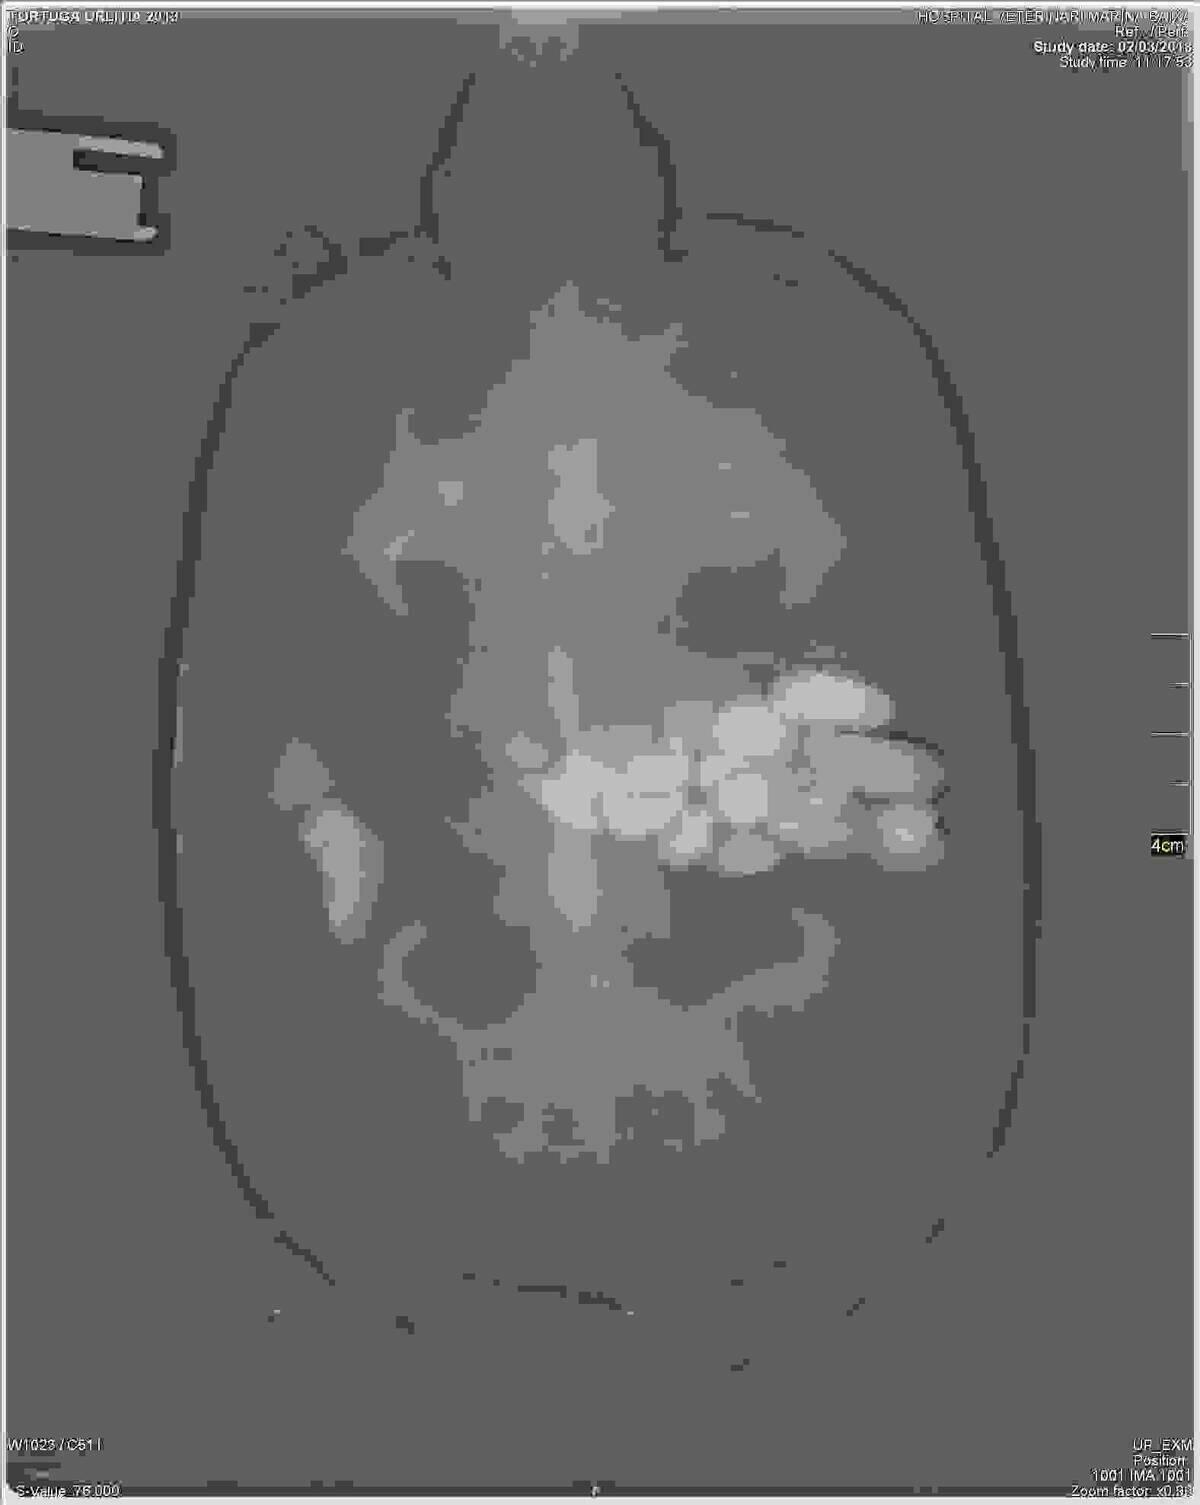

La tortuga fue trasladada al Hospital Veterinario Marina Baixa, donde el veterinario José Rial se encargó del examen y de practicar la operación. En la radiografía se detectó la presencia de cuerpos extraños en el estómago, que por su forma y tamaño hizo sospechar a los veterinarios que se trataba de piedras que generaban los problemas de flotabilidad al animal.

En total, se extrajeron unas 25 piedras de entre uno y tres gramos de peso. Los cuidadores creen que la ingesta de las piedras puede deberse a que hay algunas tortugas que lo hacen para aportar minerales a su organismo o a que este ejemplar haya adquirido el vicio de ingerir objetos que no pertenecen a su dieta habitual. De hecho, se trata de la primera vez que ocurre.